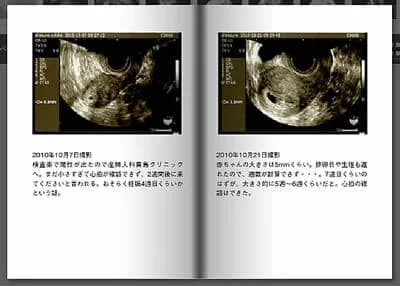

エコー写真を時系列に並べた成長記録

一番初めのエコー写真から誕生、その後を時系列でアルバムで並べるというシンプルな方法です。成長過程を追うことで何とも言えない感動がこみ上げてくるでしょう。将来、生まれてきた子どもと見返す。その瞬間も、かけがえのない時間になりますね。

エコー写真の記号は妊娠週数と赤ちゃんの大きさを表しています。 以下の記号と意味を参考にし、赤ちゃんの成長を実感してみてください!

AGEまたはGA:検査日の妊娠週数(w:週、d:日)

CRL:赤ちゃんの頭からおしりまでの長さ(mm)

BPD:頭の左右で最も広い部分(mm)

APTD:お腹の前後の厚み

TTD:お腹の左右の幅

AC:お腹周りの長さ

EFW:推定体重

FL:大腿骨の長さ

これらの記号と一緒にエコー写真をアルバムに整理しておくと、振り返ったときに赤ちゃんの成長過程がより分かりやすくなります。